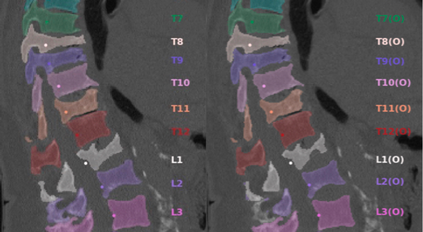

Vertebrae localization, segmentation and identification in CT images is key to numerous clinical applications. While deep learning strategies have brought to this field significant improvements over recent years, transitional and pathological vertebrae are still plaguing most existing approaches as a consequence of their poor representation in training datasets. Alternatively, proposed non-learning based methods take benefit of prior knowledge to handle such particular cases. In this work we propose to combine both strategies. To this purpose we introduce an iterative cycle in which individual vertebrae are recursively localized, segmented and identified using deep-networks, while anatomic consistency is enforced using statistical priors. In this strategy, the transitional vertebrae identification is handled by encoding their configurations in a graphical model that aggregates local deep-network predictions into an anatomically consistent final result. Our approach achieves state-of-the-art results on the VerSe20 challenge benchmark, and outperforms all methods on transitional vertebrae as well as the generalization to the VerSe19 challenge benchmark. Furthermore, our method can detect and report inconsistent spine regions that do not satisfy the anatomic consistency priors. Our code and model are openly available for research purposes.